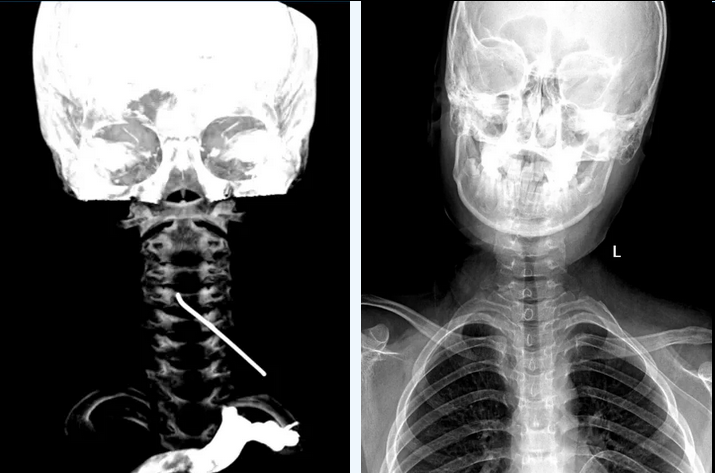

A 10cm metallic foreign body with a hooked tip was lodged in the cervical canal of a 12-year-old.

The object penetrated via the intervertebral foramen, resting between the spinal cord and the vertebral artery.

Pre-operative reconstruction simulated the penetration trajectory.